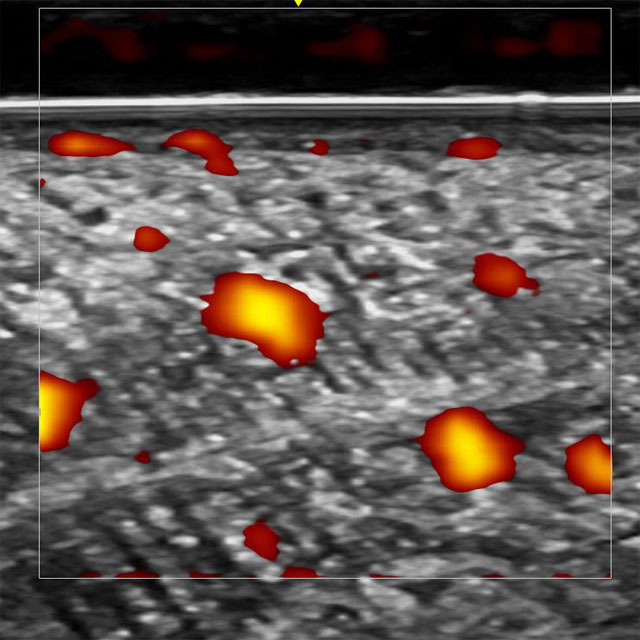

正常舌右側縁の超音波横断像(パワードプラ)